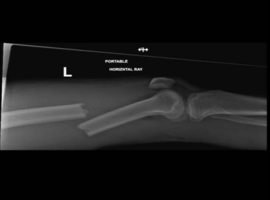

Citation: Konan S, Kejriwal R. Femoral Shaft Fracture with Ipsilateral Knee Dislocation and Popliteal Artery Occlusion: A Case Report. Case Rep Orthop Surg J. 2025; 4(4): 155.